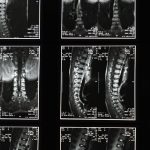

Un bombement discal se produit lorsque le disque intervertébral, situé entre les vertèbres, se déforme sans rupture. Ce phénomène peut entraîner une Compression des racines nerveuses, provoquant douleur, engourdissement, ou faiblesse dans les membres. Il est essentiel de traiter cette condition pour éviter des complications supplémentaires.

Un bombement discal se produit lorsque le disque intervertébral, qui agit comme un amortisseur entre les vertèbres, commence à s’étirer au-delà de ses limites normales. Contrairement à une hernie discale, le matériau gélatineux à l’intérieur du disque ne s’échappe pas de sa capsule, mais la protrusion peut toujours exercer une pression sur les nerfs environnants, entraînant douleur et inconfort. Cette condition peut affecter n’importe quelle partie de la colonne vertébrale, mais elle est plus fréquente dans la région lombaire.

Le bombement discal, une condition où un disque intervertébral se gonfle mais ne se rompt pas, peut entraîner des douleurs importantes, des engourdissements et d’autres symptômes neurologiques. Pour remédier à cette problématique, la décompression neurovertébrale émerge comme une méthode non invasive et efficace. En utilisant une technologie avancée, cette technique permet de relâcher les tensions sur la colonne vertébrale et de favoriser la guérison des disques endommagés.